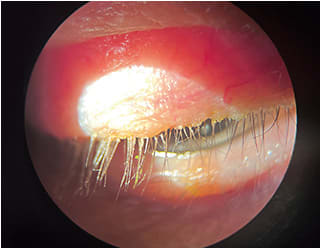

I was challenged a few years ago to have my patients look down during the slit lamp exam to enable me to evaluate the upper lid margin for collarettes, a pathognomonic sign of Demodex blepharitis. It was an eye-opening experience (pun intended), as I realized I had likely missed diagnosing several patients who had the condition. The scientific literature also bears this out.

Specifically, a recent multicenter retrospective study shows that 57.7% of patients had Demodex blepharitis, as confirmed by the presence of collarettes.1 Interestingly, 77% of those patients who had Demodex blepharitis presented for an annual exam, cataracts, and glaucoma, not for complaints, such as dryness, tearing, burning, stinging, or itching, related to Demodex blepharitis.1 This study illustrates that if we look for the presence of Demodex blepharitis based solely on patient complaints, we will miss a large majority of these diagnoses.

A 2022 study revealed that eyelids with collarettes had significantly more meibomian gland atrophy on meibography than those without.2 Additionally, those eyes that had more severe Demodex blepharitis had significantly more telangiectasia and meibomian gland atrophy when compared to patients with less severe Demodex blepharitis.2